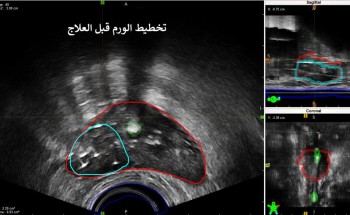

فريق طبي يتمكن من علاج ورم في غدة البروستات.. ورئيس الفريق الدكتور “سعد الرشيدي”: المريض تلقى 39 جلسة من العلاج الإشعاعي الخارجي

تمكن فريق طبي من مركز الأورام الشامل في مدينة الملك فهد الطبية إحدى مكونات تجمع الرياض الصحي الثاني من علاج ورم في غدة البروستات، بواسطة العلاج الموضعي الجزئي (براكي ثيربي) باستخدام أجهزة متقدمة موجهة بالأشعة ...